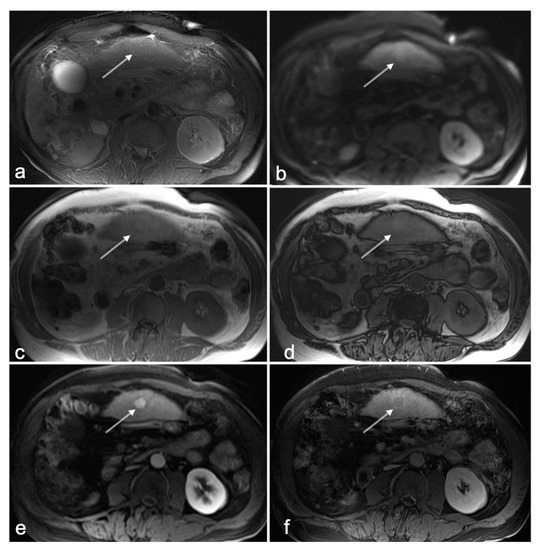

3.2. HCC-Naïve Cases